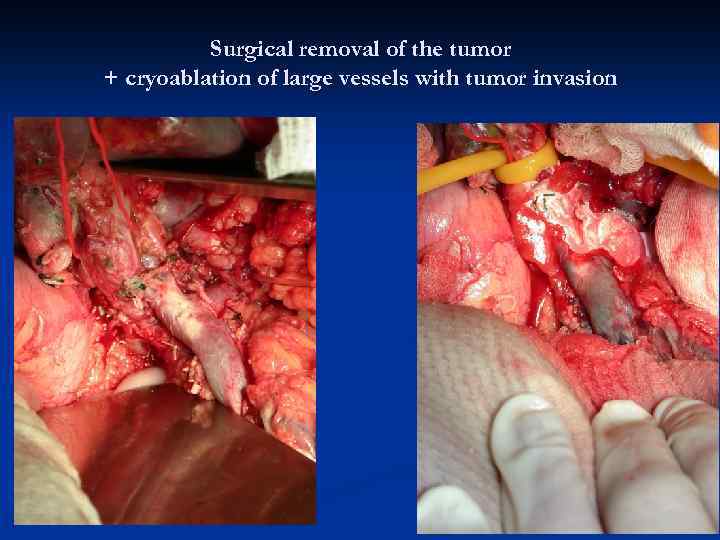

Surgical removal of the tumor + cryoablation of large vessels with tumor invasion

Surgical removal of the tumor + cryoablation of large vessels with tumor invasion